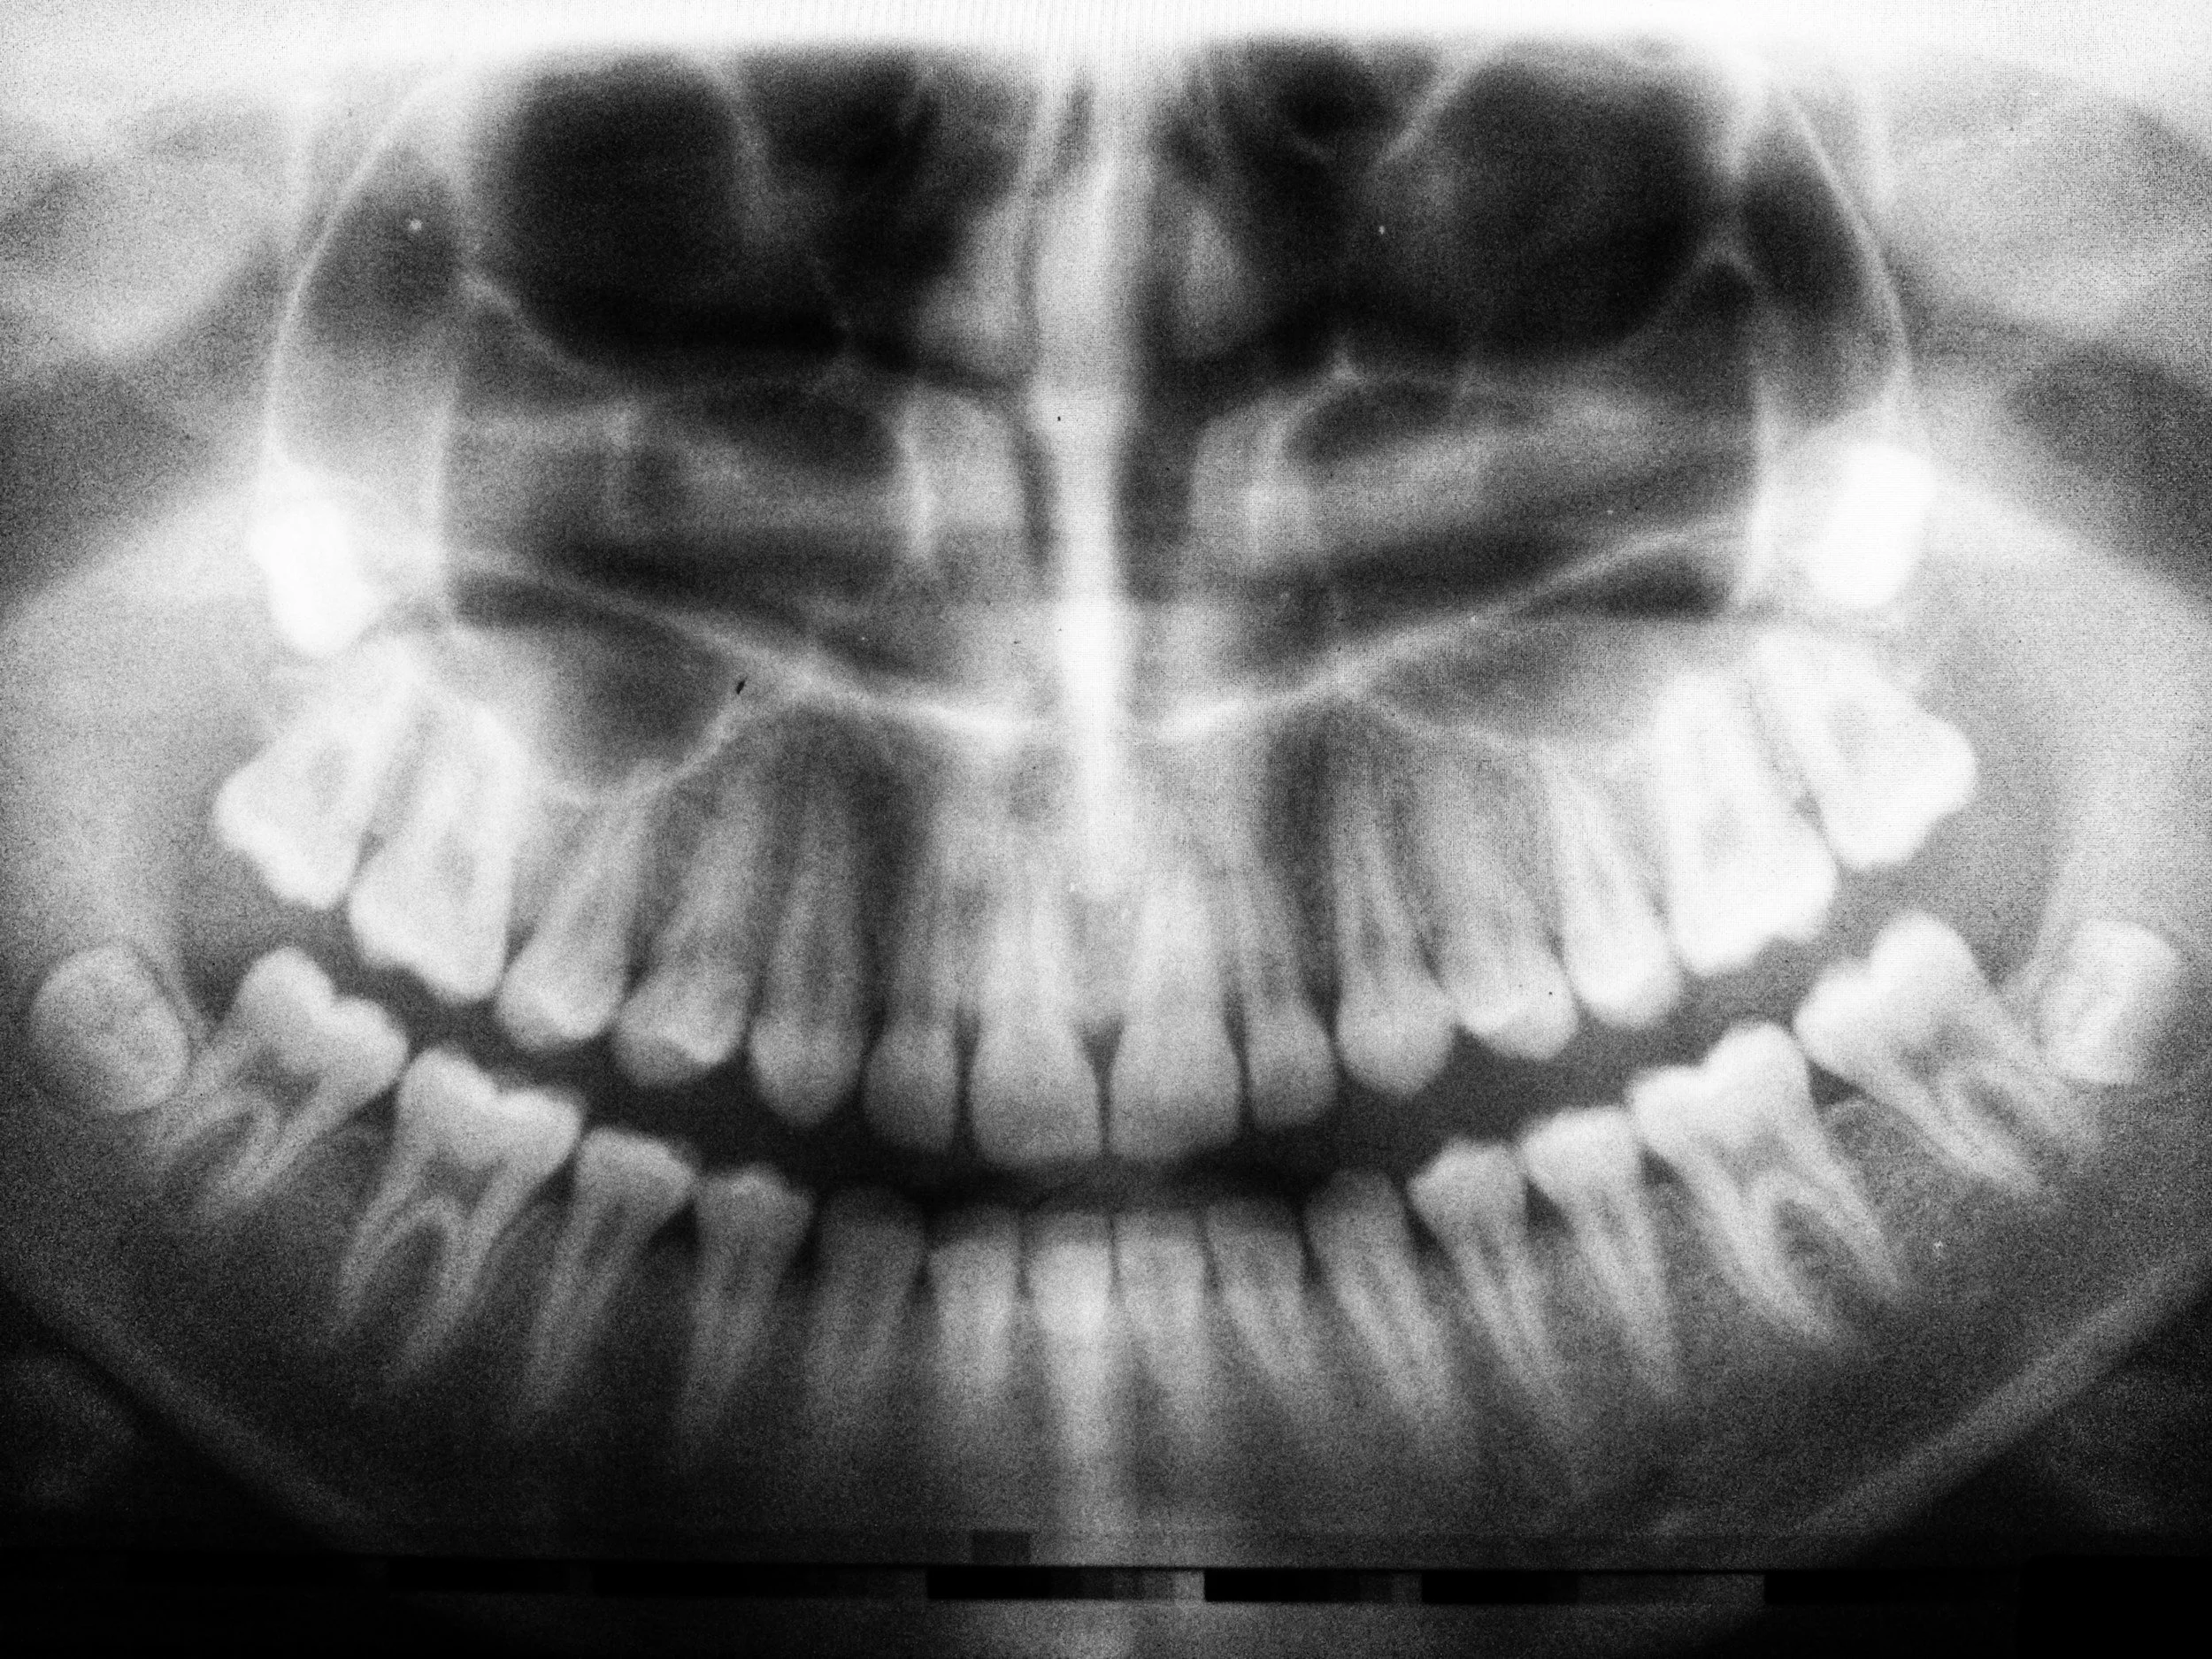

Wisdom tooth extractions typically cost between $450 and $900 per tooth, depending on whether the extraction is simple or requires surgery (e.g., if the tooth is impacted). We’ll take X-rays and provide a detailed quote before any treatment.